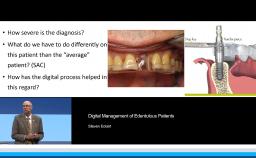

This lecture describes the treatment approach using a digital workflow for fixed implant rehabilitation of edentulous jaws. Treatment sequence, implant number and distribution, and the implant-prosthetic design are all thoroughly discussed. The speaker presents a detailed approach to full-arch rehabilitation using the digital workflow, which includes immediate loading with fixed screw-retained provisional prostheses during the healing phase. Other techniques presented include use of transitional implants and segmentation of full-arch prostheses. Evidence is presented on digital versus conventional implant impressions and the anterior-posterior distribution of implants in relation to survival.

- describe the appropriate number and location of implants in the fixed rehabilitation of the edentulous patient

- discuss the advantages of virtual planning to reduce risk of failures

- describe the various approaches in rehabilitating the edentulous patient using the digital work flow